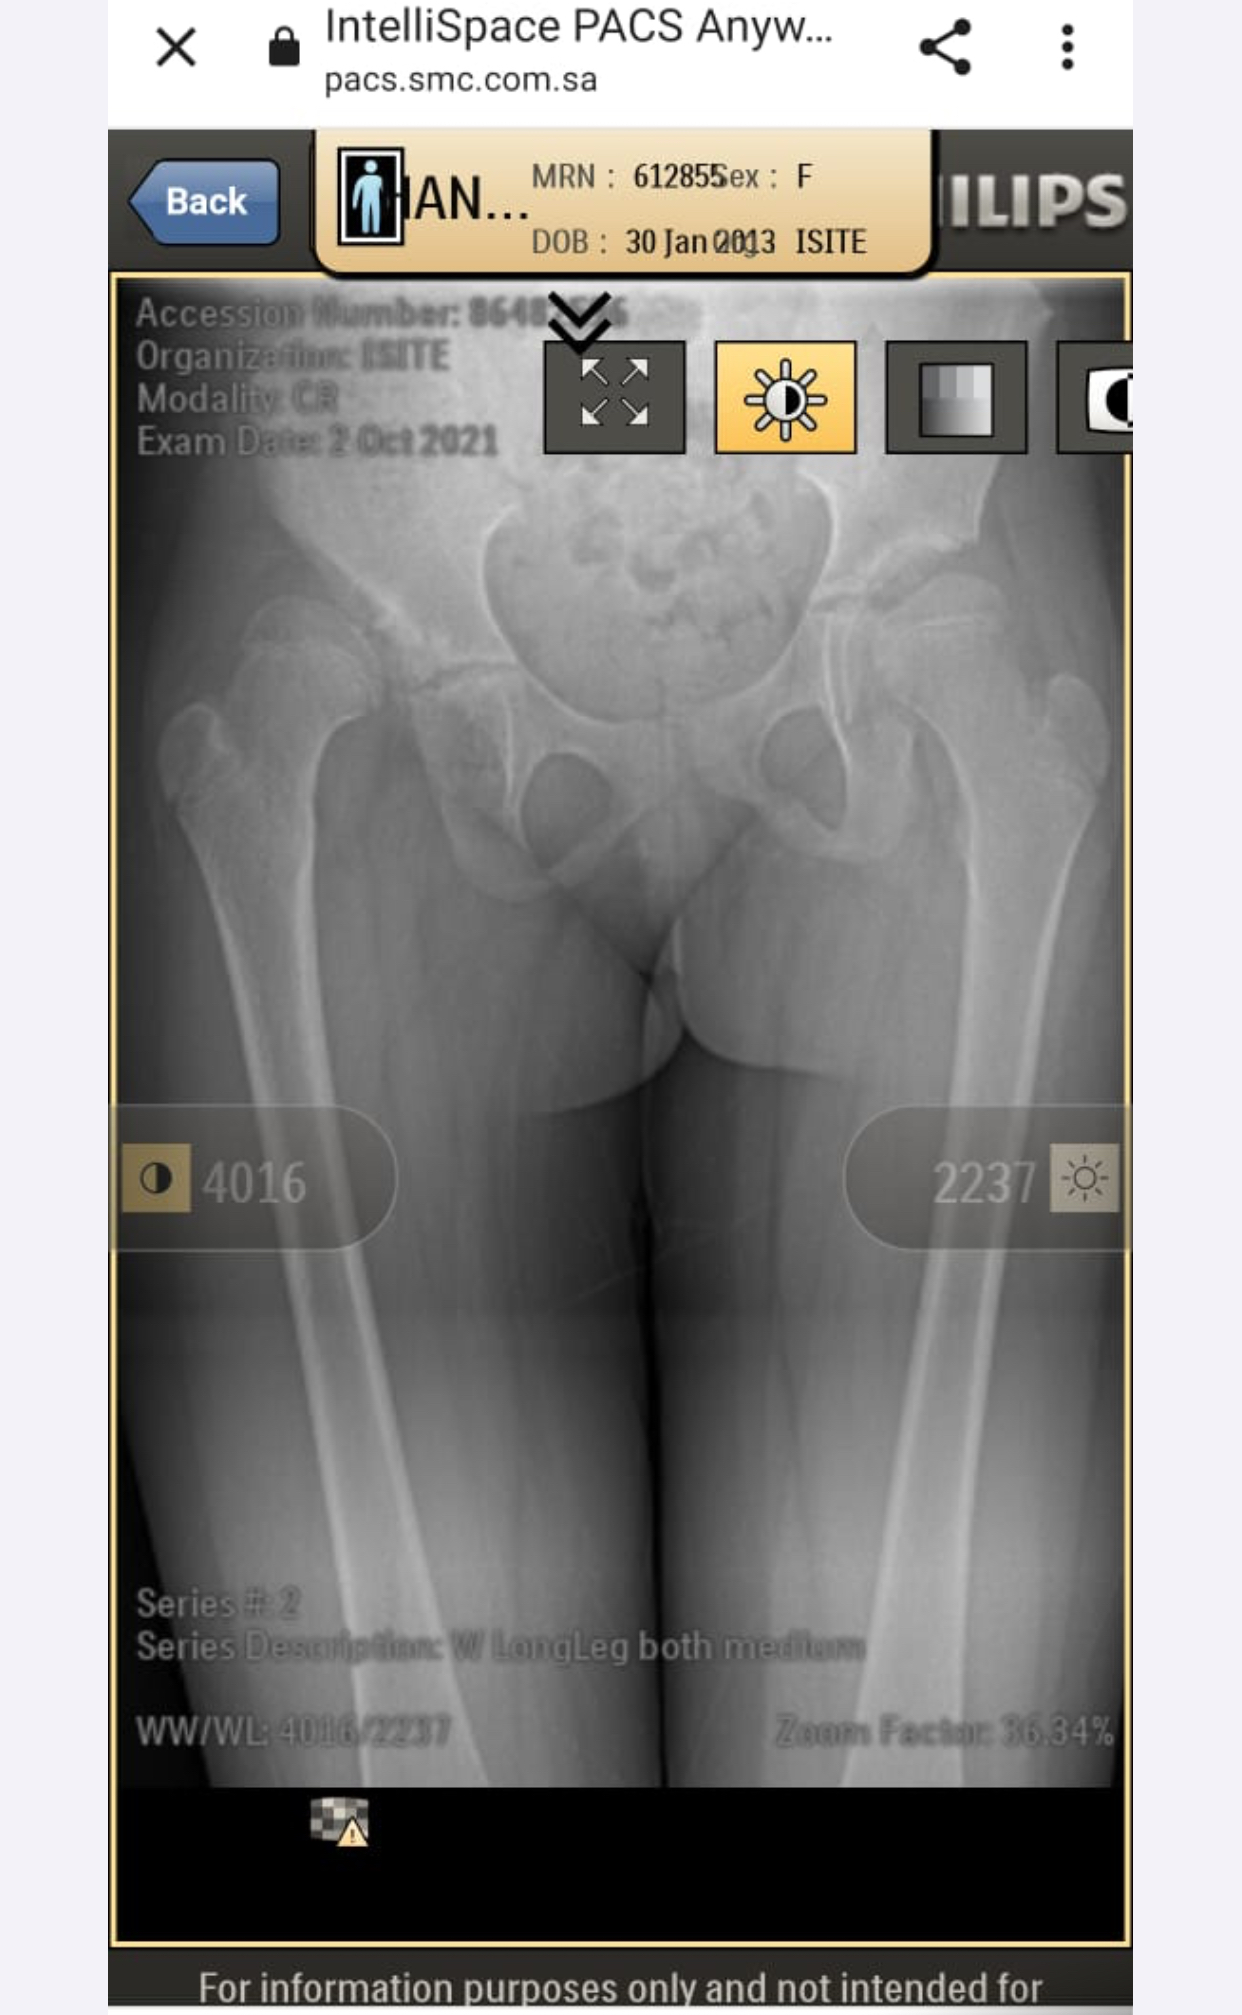

My daughter is diagnosed with hip dysplasia at age of 8.8 years. Doctor is saying for surgery immediately but we got another opinion and that surgeon is saying that there is no success rate of surgery right now. You have to wait once she grow up n then we will go for hip replacement. While the other doctor is saying that surgery is must. We need an opinion on it. Xrays are attached

she definitely need surgery to keep the head at level of socket. you should consult DR. CHIRAGH at GHURKI TRUST HOSPITAL, LAHORE. He is very experienced and expert for this disease.

it needs operation as soon as possible.

Surgery at present at 9yrs of age won't result good results. And re-dislocation may occur soon after surgery. Wait for maturity and then go for translational osteotony/replacement surgery.

need surgery as soon as possible

Salam, She needs to get MRI of hip joint to measure angles related to hip dysplasia and clinical exam as well before deciding surgery. Thanks